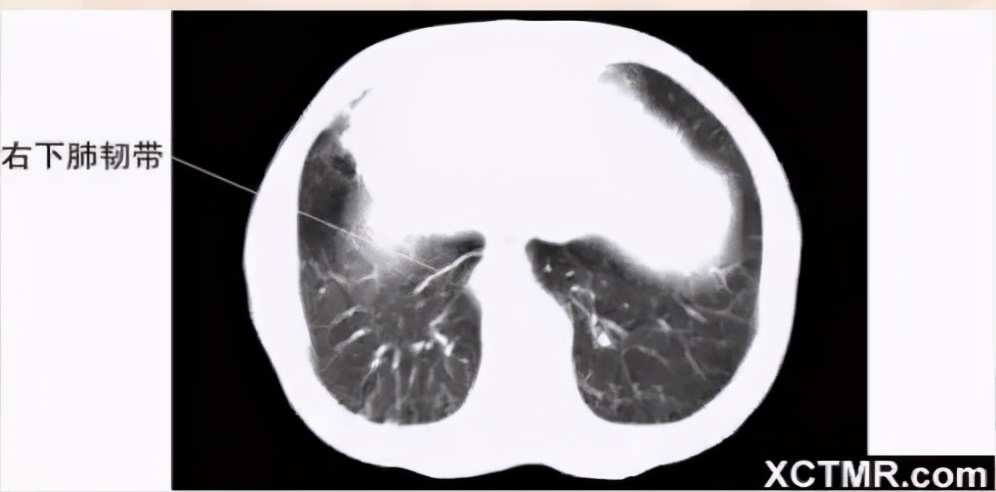

肺窗